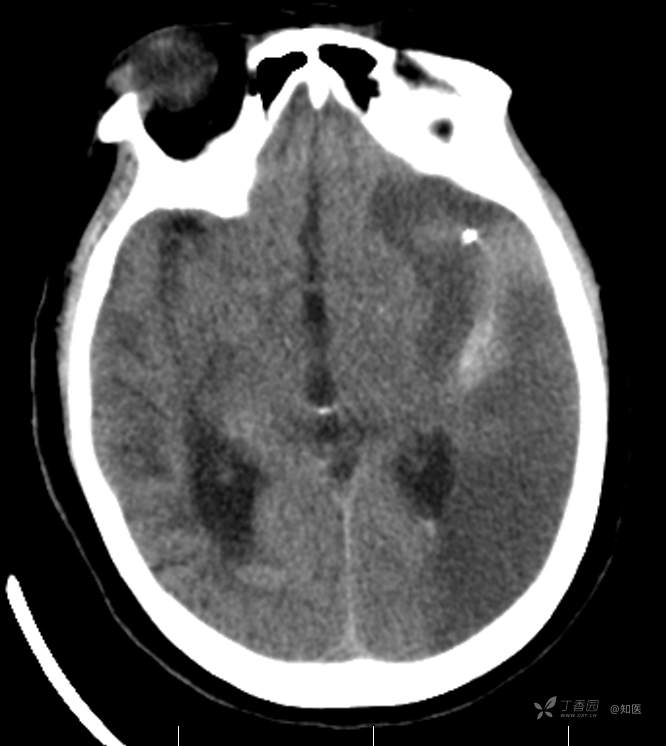

4-22日查房患者呈昏睡状,混合性失语,右侧肢体肌力障碍较入院时加重,胃肠减压引流物为深黄绿色液体,量约150ml。查体:GCS 9分(睁眼反应 3分+语言 1分+运动 5分),NHISS评分23分(意识水平 2分+提问 2分+指令 1分+凝视 2分+面瘫2+左上肢 1分+右上肢4分+左下肢 2分+右下肢4分+语言 3分),昏睡状,查体欠合作,混合性失语,粗测智能查体不配合。双眼闭目紧,双侧球结膜水肿,双侧瞳孔等大等圆,直径约4.0mm,对光反射灵敏,眼球无自主运动,无眼震,右侧鼻唇沟浅,口角向左歪斜。咽部查体不配合。转颈、耸肩查体不配合。伸舌不配合。右上肢肌力1级,右下肢肌力2级,左上肢肌力3级,左下肢肌力4级,四肢肌张力减低。四肢深浅感觉及共济运动查体不配合。右侧巴氏征阳性,左侧巴氏征阴性。颈抵抗。双侧布氏征及克氏征均阴性。辅助检查:头颅+胸部CT:与前片(2021-4-21 13:57)对比,现片示:1、环池、桥前池及大脑镰后部及小脑幕高密度影,考虑出血,较前新发。2、额颞顶叶高低混杂密度影,考虑梗塞伴造影剂残留;左侧大脑中动脉走行区致密影,系术后改变;请结合临床。3、多发腔梗,脑白质脱髓鞘,脑萎缩。4、双肺间质性改变,双肺下叶纤维索条,双侧胸腔微少量积液征象,双侧胸膜增厚。5、主动脉及冠状动脉管壁多发钙化斑块。三线主任医师、二线主治医师查房后示:根据患者病史、体征及辅助检查,目前诊断:1.脑梗死出血转化;2.左侧大脑中动脉次全闭塞;3.左侧大脑中动脉支架植入术后;4.高血压2级(很高危);5.2型糖尿病;6.应激性溃疡伴出血。目前病情及治疗上需注意以下问题:1.患者出血转化,增加脱水剂剂量,调整为20%甘露醇 125ml 每8小时一次、甘油果糖 250ml 每12小时一次,同时结合患者球结膜水肿,白蛋白正常低值,今日给予补充人血白蛋白10g,注意监测电解质等变化。2.患者为蛛网膜下腔出血,给予泵入尼莫地平预防脑血管痉挛。3.患者左侧大脑半球见大片脑白质脱髓鞘,考虑脑白质营养不良,给予维生素B1、维生素B12、维生素C、维生素B6及依达拉奉改善微血管通透性;4.患者出现应激性溃疡伴出血,今日暂禁食,给予泮托拉唑抑酸及肠外营养补充,密切观察消化道出血情况,根据病情变化调整抑酸药物剂量及频次;5.患者卧床,今晨见明显痰多,给予化痰等对症处理,监测血常规及脓毒症2项指标。6.向家属再次告知病情,因患者高龄、既往高血压及糖尿病病史,此次治疗出现出血转化,存在意识障碍加深、病情加重可能。7.密切观察神经系统体征变化。遵嘱执行。

4-23日查房:患者呈中度醒状昏迷,右侧肢体肌力障碍较入院时加重,胃肠减压引流物为黄绿色液体,量约200ml。入院后至今晨入量为4050ml,出量为4850ml。查体:GCS 6分(睁眼反应 2分+语言 1分+运动 3分),NHISS评分35分(意识水平 3分+提问 2分+指令 2分+面瘫3分+左上肢 4分+右上肢4分+左下肢 4分+右下肢4分+感觉 2分+语言 3分+构音障碍 2分+忽视 2分)。中度昏迷。双目睁眼状,双侧球结膜水肿较昨日明显,双侧瞳孔等圆,不等大,右侧直径约3.5mm,左侧瞳孔直径约3.0mm,对光反射灵敏,眼球无自主运动,无眼震。右侧鼻唇沟浅,口角向左歪斜。咽部查体不配合。转颈、耸肩查体不配合。伸舌不配合。四肢肌力检查不配合,右上肢落鞭征阳性,左上肢落鞭征阴性,右下肢不能撑于床面,左下肢可撑于床面,四肢肌张力减低。四肢深浅感觉及共济运动查体不配合。右侧巴氏征阳性,左侧巴氏征阴性。颈抵抗。双侧布氏征及克氏征均阴性。辅助检查:经颅多普勒示:左侧大脑中动脉峰值流速极低,右侧大脑中动脉及双侧大脑前动脉血流速度未见明显异常。头颅CT(2021-04-22):与前片(2021-4-21)对比,现片示:1.环池、桥前池及大脑镰后部及小脑幕高密度影,较前减少。2.额颞顶叶高低混杂密度影,考虑梗塞伴造影剂残留;左侧大脑中动脉走行区致密影,系术后改变;基本同前。请结合临床。3.多发腔梗,脑白质脱髓鞘,脑萎缩。同前。二线主治医师查房后示:患者目前诊断明确。现治疗上需注意以下问题:1.患者夜间体温上升,最高38度,结合患者卧床、痰多、不易咳出,且化验检查提示炎性指标较前明显升高,今日给予头孢哌酮舒巴坦抗感染治疗,同时继续雾化祛痰等。2.因患者应激性溃疡并出血,昨日查胃液潜血阳性,但经给予泮托拉唑抑酸护胃治疗后消化道出血未进行性加重,胃管引流物为黄绿色液体,今日暂继续给予氨基酸、脂肪乳等肠外营养支持,安排再次复查胃液潜血,若转阴可给予肠内营养加强支持治疗。3.患者血压仍有偏高,夜间泵入乌拉地尔控制,今日给予左氨氯地平平稳控制血压,监测血压变化。4.患者昨日血糖波动在6.8-11.4mmol/l,结合其糖化血红蛋白为6.4%,暂不干预血糖,继续监测血糖变化。5.患者意识障碍程度加重,双侧瞳孔不等大,但光反射灵敏,考虑与脑梗死后水肿高峰有关,治疗上继续加强脱水,向家属再次详细告知病情及目前诊疗方案,存在颅内压增高至脑疝形成、呼吸心跳骤停可能,表示理解知情。密切观察生命体征及神经系统体征变化。遵嘱执行。